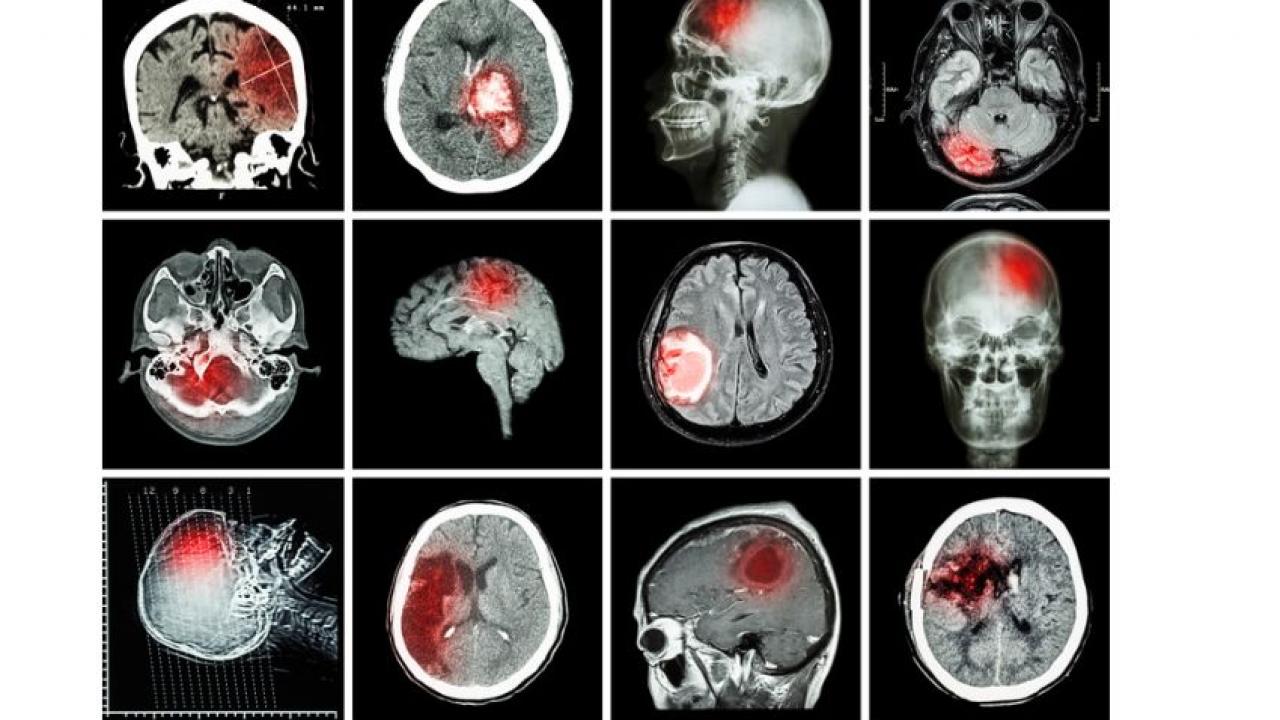

İnme, beyin damarlarında meydana gelen tıkanıklık veya kanama nedeniyle beyin hücrelerinin hasar görmesiyle oluşan bir hastalıktır. Beyin hücreleri oksijen ve besin maddeleri alamadığında zarar görür ve bu da belirtilere yol açar. İnme, beyne giden kan akışının kesilmesi sonucu meydana gelen iskemik inme veya beyin damarlarında meydana gelen kanama sonucu meydana gelen hemorajik inme şeklinde ortaya çıkabilir. İnme, özellikle yüksek tansiyon, sigara kullanımı, kalp hastalığı, yüksek kolesterol, diyabet gibi risk faktörleri olan kişilerde daha sık görülür. İnme, hızlı müdahale edilmediği takdirde ölümcül olabilir ve uzun süreli sakatlıklara yol açabilir. Bu nedenle, inme belirtileri fark edildiğinde acil tıbbi yardım alınması şart koşuluyor.

İnme tedavisi, hastalığın tipine ve şiddetine bağlı olarak değişebiliyor. İskemik inme tedavisi genellikle kan pıhtılarını eritmeye yardımcı olan ilaçların kullanımını içerir. Bu ilaçlar, pıhtının erimesine yardımcı olarak kan akışının düzeltilmesine yardımcı olur. Bazı hastalarda, kan pıhtısını doğrudan çıkarmak için cerrahi müdahale gerekebiliyor.

Hemorajik inme tedavisi, kanama kaynağının kontrol edilmesini ve kanama bölgesinin küçültülmesini içerebilir. Cerrahi müdahale, kanama bölgesini boşaltmak veya kanama kaynağını kapatmak için yapılıyor.